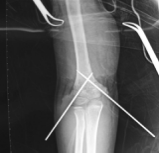

胫骨中1/3稳定型骨折:横形骨折、短斜形骨折、假关节。

胫骨中部60%长度内的不稳定性骨折:干骺端附近的骨折、长螺旋形骨折、节段性骨折、粉碎性骨折、骨折伴骨缺损。

多用于胫骨中段骨折。尽管也可用于胫骨近端和远端骨折,但并发症发生率较高,易发生畸形愈合。